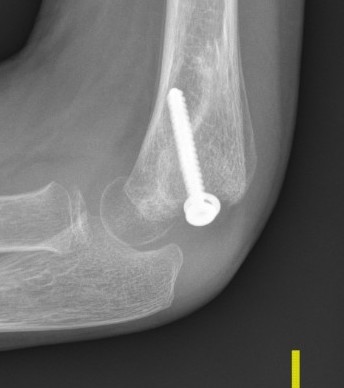

Open reduction of displaced lateral condyle in left elbow

K wires v screws

Screw

- compression of fragment

- potentially less non union

- more difficult to remove

- 60 patients treated with lag screws or K wires

- no difference in outcome

- less stiffness in screw fixation due to earlier mobilisation

In situ screw fixation delayed nonunion